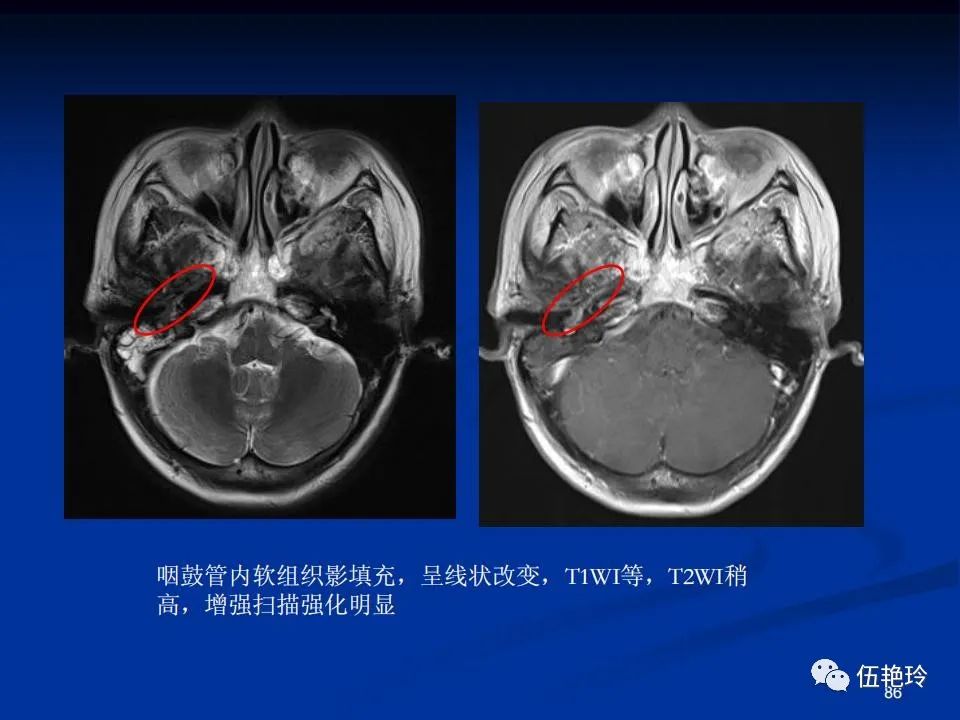

耳与面神经的解剖